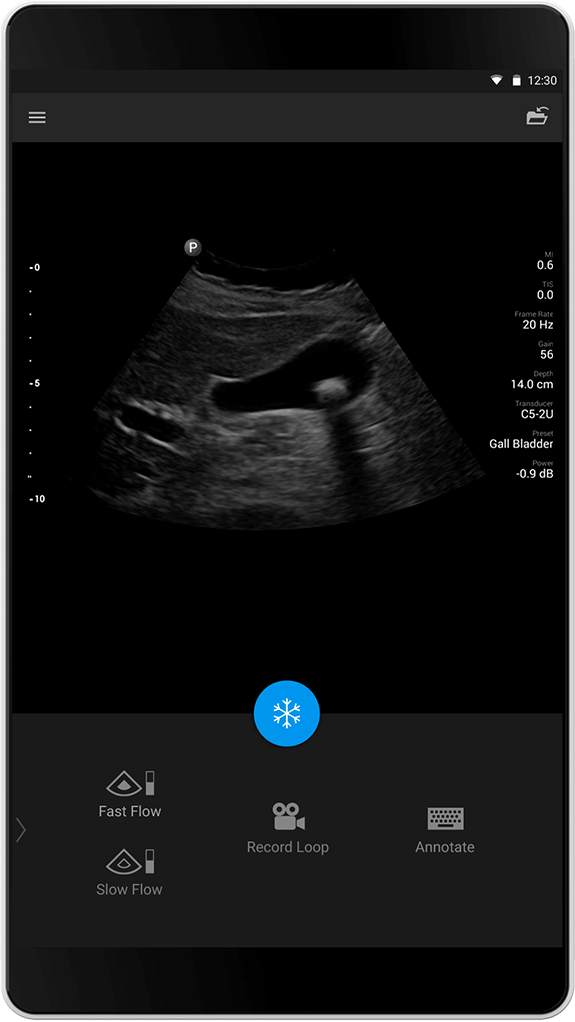

Forhåndsinnstillingen Gallbladder (Galleblære) er optimalisert for å gi god penetrasjon, som vil gi god oppløsning for galleblæren. Denne forhåndsinnstillingen er perfekt til å påvise patologisk fortykning av galleblæreveggene samt gallestein.